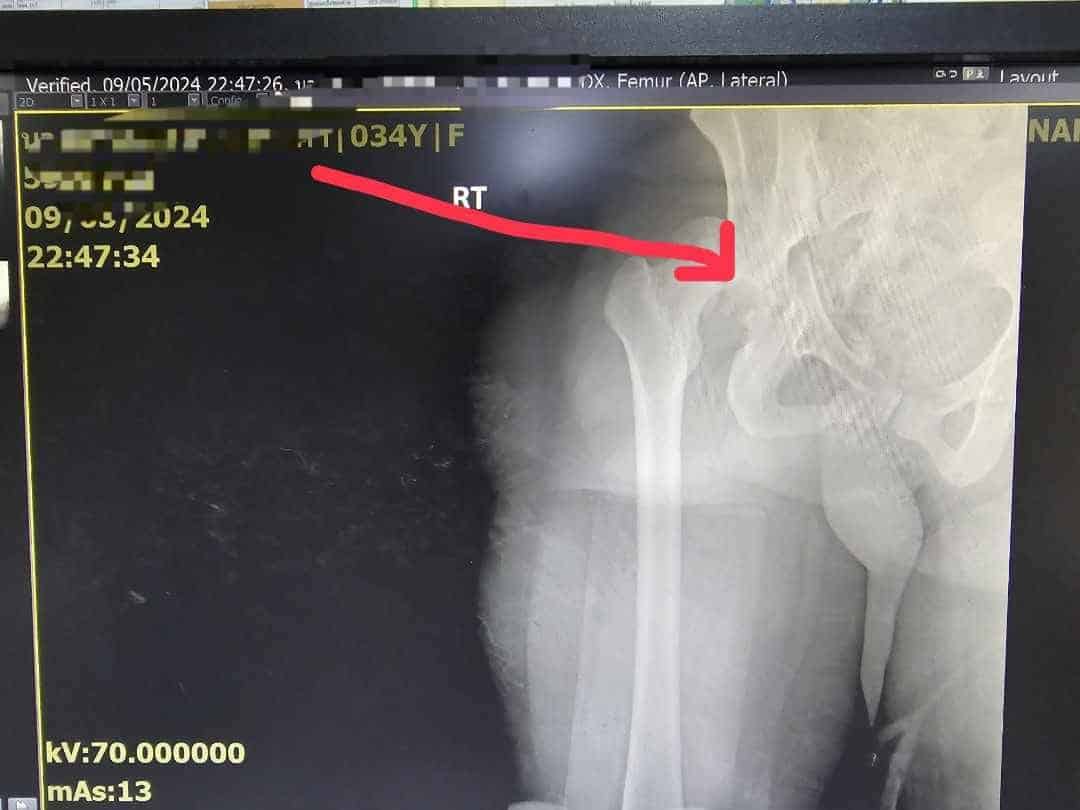

โดยพยาบาลรีเฟอร์รายนี้ได้รับบาดเจ็บสาหัส ตอนถูกนำตัวมาส่งมีอาการเลือดออกในสมอง ใบหน้าด้านขวาบวม หูซ้ายฉีก กระดูกนิ้วก้อยหักเเบบมีเเผลเปิด กระดูกสะโพกขวาหลุด กระดูกเชิงกรานหัก